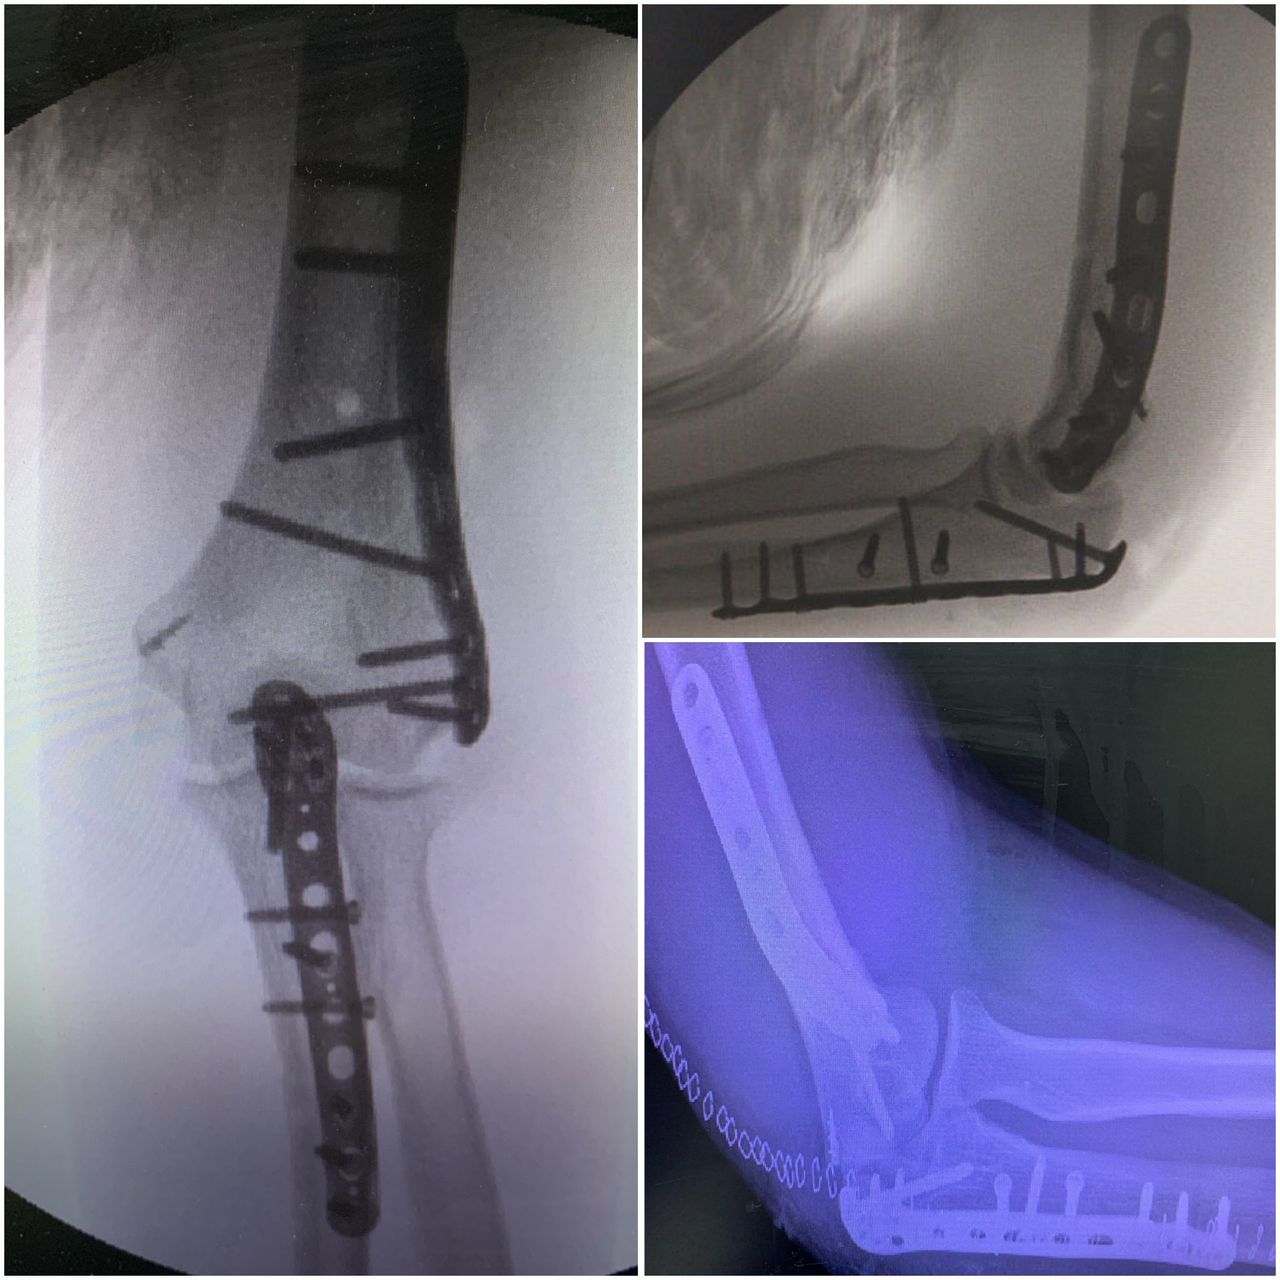

Se especializa en Síndrome del Manguito Rotador, Artroscopía de Hombro, Luxación de Hombro, Epicondilitis Lateral (Codo de Tenista), Fractura de Clavícula, Disyunción Acromioclavicular, Fracturas de Codo.

Conferencista. Tríada Terrible del Codo. II Jornadas de Traumatología. Hospital Universitario de Caracas (HUC). Caracas, Venezuela. 2015